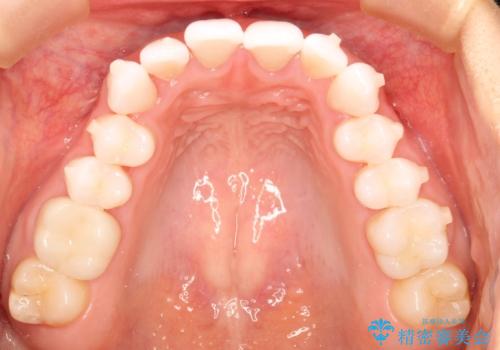

気になる前歯の歯並びをインビザラインで矯正

- 前歯の傾きと、ガタガタが気になるとのことで来院されました。

前歯の傾きや高さをシミュレーションで患者様と確認しながら、歯並びを仕上げていきました。

遠方での合宿などで長期に来院できない場合も、インビザラインなら治療が可能となります。